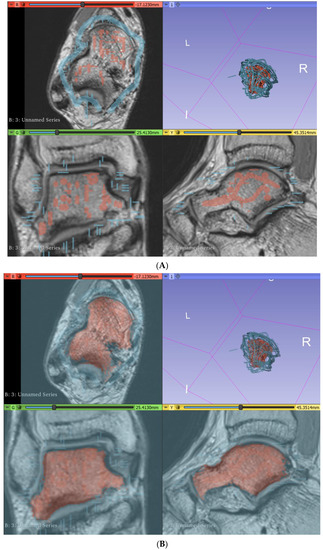

2.3. Segmentation of Musculature

2.4. Creation of Mixed Reality